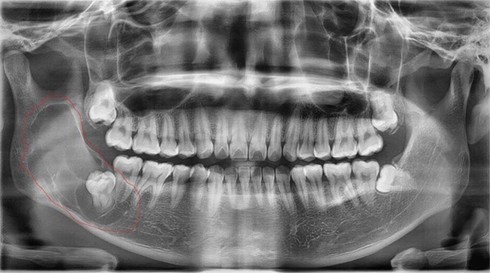

Bác sĩ Nguyễn Thanh Thái, Trưởng khoa Phẫu thuật tạo hình hàm mặt, cho biết kết quả chụp X-quang cho thấy bệnh nhân bị nang răng sừng hóa (còn gọi nang răng sinh sừng). Nang rất lớn, phát triển từ răng số 7 lan lên tới tận xương hàm trên.

Theo bác sĩ Thái, nang răng sừng hóa thường hình thành do nhiễm khuẩn, hay gặp ở độ tuổi 30. Ở giai đoạn sớm, bệnh nhân không có triệu chứng nào, đến khi nang to sẽ bội nhiễm gây đau đớn và dễ nhầm lẫn với mọc răng khôn.

Nhiều trường hợp đến viện muộn, nang đã phát triển rộng khiến cho răng, xương bị phá hủy gây biến dạng khuôn mặt. Một số ít bệnh nhân phát hiện sớm do tình cờ đi kiểm tra, chụp X-quang răng miệng.

Bác sĩ Thái cho biết tỷ lệ tái phát nang răng sừng hóa rất cao, lên tới 60%. Vì vậy, bệnh nhân thường phải phẫu thuật nhiều lần do bệnh tái phát sau khi nạo vét các tổ chức u. Bác sĩ chỉ lấy được chân nang chứ không thể tiêu diệt mầm bệnh tận gốc.